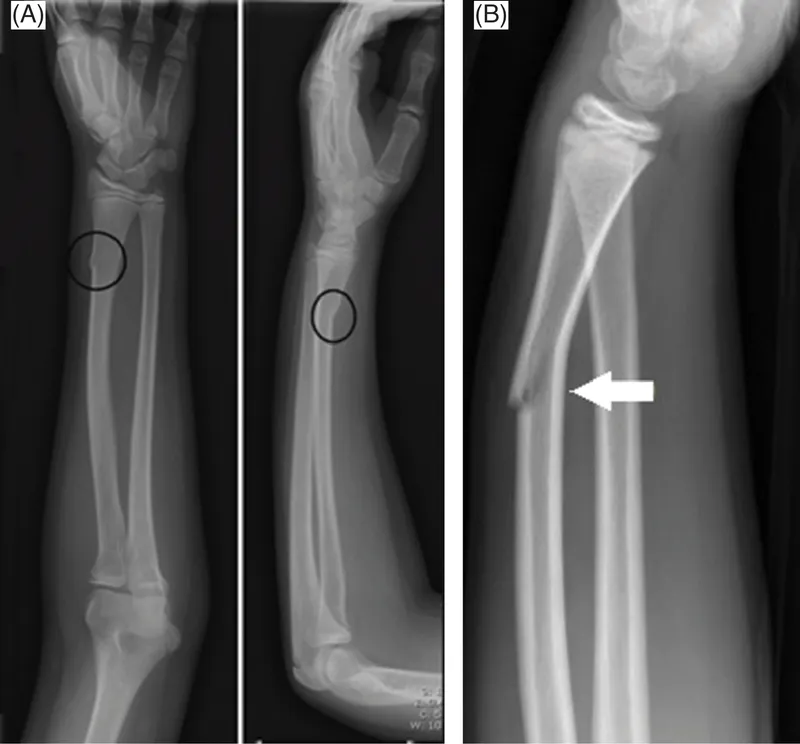

- Incomplete Fractures (Elastic bones):

- Torus/Buckle: Compression causes cortex to bulge.

- Greenstick: Tension side breaks, compression side bends.

- Plastic Bowing: Bone bends, no distinct fracture line.